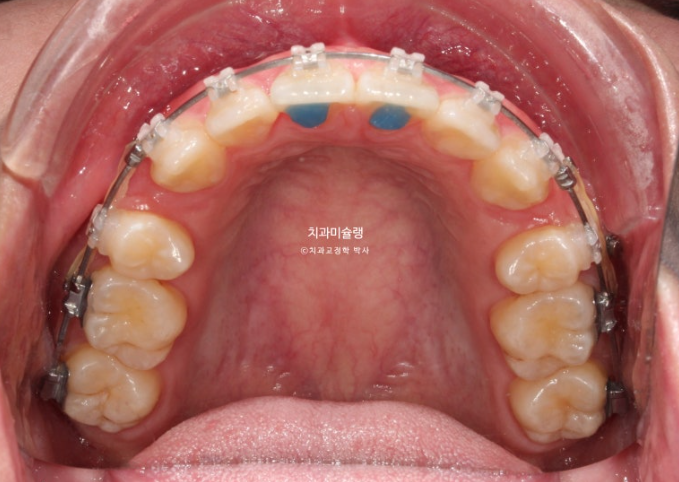

앞니를 합입시키는 과정에서 잇몸이 치아와 함께 잘 따라 올라가기도 하고, 치아 높이가 처음에 비해 짧아지기도 합니다.

후자의 경우는 교정 후 잇몸성형이 필요합니다.

25.11

잇몸성형 직후 모습입니다.

앞니 3개에만 시행했습니다.